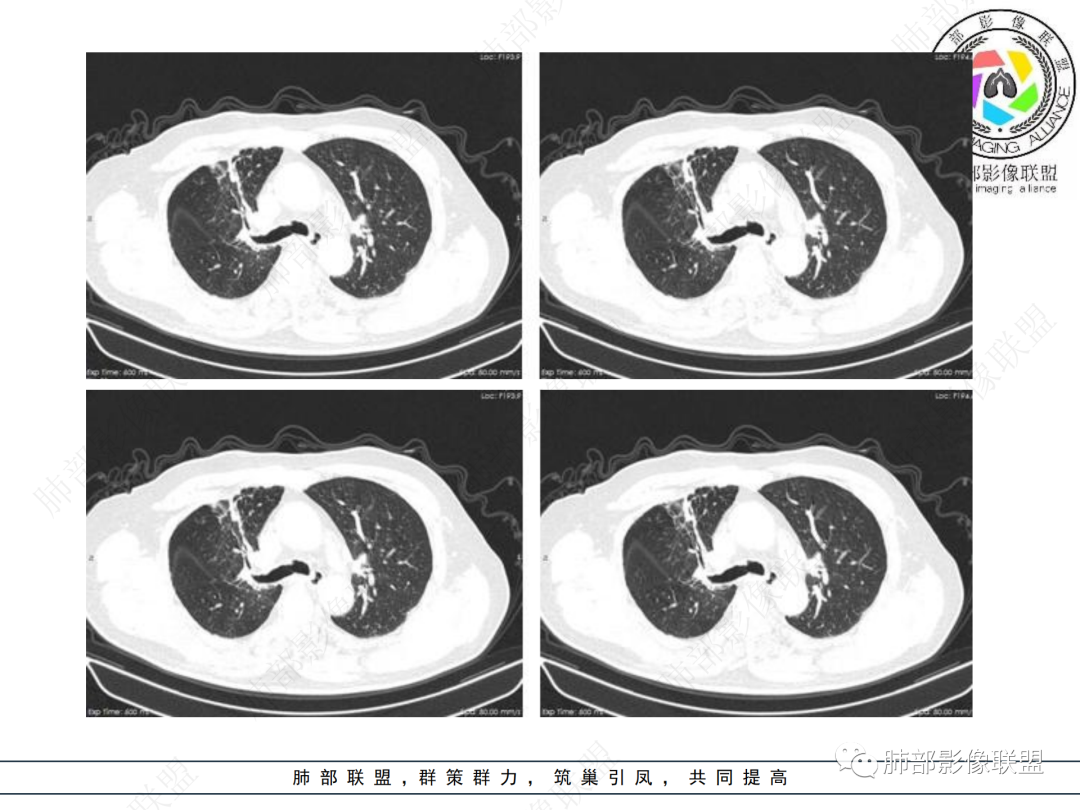

右肺上叶可见一团块影,边界清,有膨隆有凹陷,边缘可见毛刺,斜裂可见牵拉,不均匀强化,内可见液化,临近支气管未见明确阻塞,考虑腺癌可能,鉴别脓肿,结核等

右肺上叶团块,边缘毛糙,长索条,周围斑点影,邻近胸膜增厚,不均匀强化,其内小低密度灶边界清,考虑炎性肉芽肿,腺癌待排

右上胸廓缩小,叶间裂移位,尖段软组织影,前段支气管壁增厚,双上肺多发结节及条片影,增强后尖段软组织影内见多发低密度影,呈环状强化,考虑慢性肉芽肿,腺癌待排

男性,69岁 反复咳嗽2年余,加重3天入院。CT示右肺上叶尖段不规则实变影,周边伴条索影,支气管未见明显堵塞,增强不均匀强化,考虑为恶性,腺癌可能

老年男性,慢性病程,右肺上叶团块影,边界清晰,边缘毛刺,脐凹征,胸膜牵拉,不均匀强化,支气管壁增厚,考虑恶性,腺癌可能,鉴别肉芽肿、结核

男,69,反复咳嗽2年,加重3天入院,右肺上叶软组织密度肿块影,边界尚清晰,边缘见毛刺及胸膜牵拉,右肺上叶支气管壁增厚,增强扫描不均匀性强化,考虑腺癌可能,鉴别炎性病变。

老年男性,右肺上叶体积小,见高密度团块,边缘模糊,并见多发长索条,增强后不均匀强化,考虑炎性肉芽肿性病变,鉴别腺癌

病程长,右肺上叶团片影,边缘毛糙,部分膨隆,长索条,周围长条索及结节,邻近胸膜增厚,不均匀强化,首先考虑炎性肉芽肿,鉴别腺癌

右肺上叶团块周围多发斑索,不均匀强化,支气管无明显堵塞,咳嗽两年,首先考虑慢性炎性病变,肺结核可能,鉴别腺癌

右肺上叶见不规则团块,边缘清晰,周围可见长索条及斑片影,胸膜顶增厚,右侧斜裂部分增厚,右上肺体积略缩小,增强后不均匀强化,考虑炎性肉芽肿性病变,结核?鉴别腺癌

右肺上叶体积变小,见不规则实性病灶,边缘有平直,长软毛刺,邻近胸膜明显增厚,叶间胸膜牵拉上提、局部凹陷;病灶周围不干净,可见长索条影;近端支气管壁略增厚。增强后增强不均匀,有低密度坏死,间隔较厚。考虑慢性炎性肉芽肿,结核可能,鉴别腺癌。

右侧胸廓变小,右肺上叶团块,边缘毛糙,长索条,周围斑点影,邻近胸膜增厚,气管不规整,密度不均,不均匀强化,考虑炎性肉芽肿,腺癌待排。

结合本病例,老年男性患者,慢性病程,急性加重,无吸烟史,影像学表现为右肺上叶尖后段斑片实变密度影,整体边界清晰,边缘平直收缩为主,周边散在纤维条索影,内部见支气管内粘液栓,血管影走形正常,没有明显破坏,增强扫描明显强化,缺乏典型分叶毛刺、胸膜改变,病灶也未显示清楚的磨玻璃勾边,病灶大而肺门纵隔未见肿大淋巴结,综合考虑慢性炎性肉芽肿可能性大。但恶性,结核能完全排除吗?我想对临床医生来说还是有很大考验的。